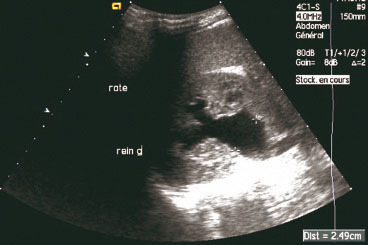

Échographie vésico-rénale. Dilatation des cavités pyélocalicielles du rein gauche en amont du calcul du bas uretère gauche. Il s'agit de signes échographiques indirects. L'échographie permet de statuer sur l'état du rein en évaluant l'épaisseur du parenchyme. Le doppler couleur peut montrer des éjaculations urétérales et confirmer la bonne vascularisation du rein.